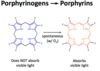

How can porphyrinogens become pathologic in Porphyria Cutanea Tarda?

Porphyrinogens can spontaneously form porphyrins

Porphyrins can then leak into blood and reach skin

Light can induce porphyrins to inflict oxidative damage